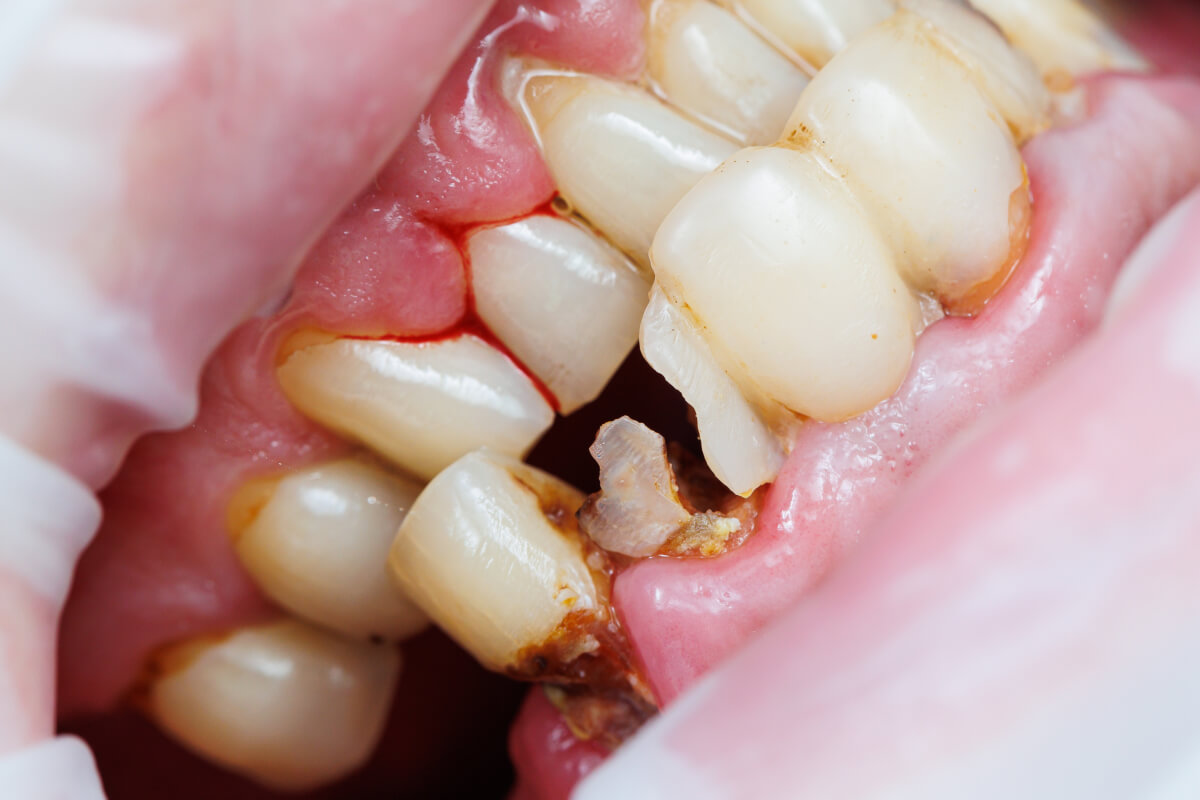

Extrakcia zuba s rozsiahlym kazom | Dental Centrum NIVY

1. Rozsiahly kaz

Ak je zub natoľko zničený, že ho už nie je možné opraviť plombou ani korunkou.